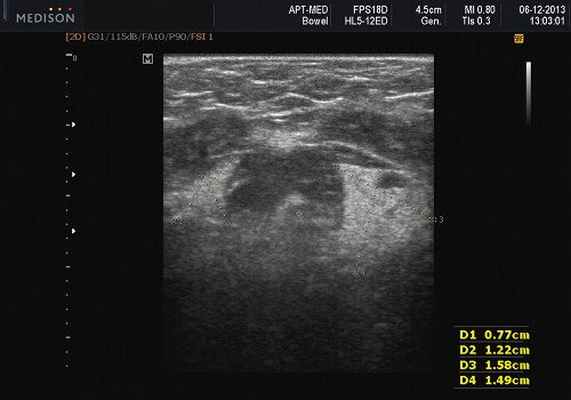

Рис. 5. Камень протока поднижнечелюстной слюнной железы.

Рис. 6. Камень в паренхиме поднижнечелюстной слюнной железы.

Рис. 7. Камень в протоке поднижнечелюстной слюнной железы.

- обструктивные сиаладениты, развивающиеся при затруднении оттока слюны при обструкции выводного протока камнем (рис. 5-7) или сгустившимся секретом, а также вследствие рубцового стеноза протока. По распространенности процесса различают очаговый, диффузный сиаладениты и сиалодохит - воспаление выводного протока. Течение процесса может быть острым и хроническим;